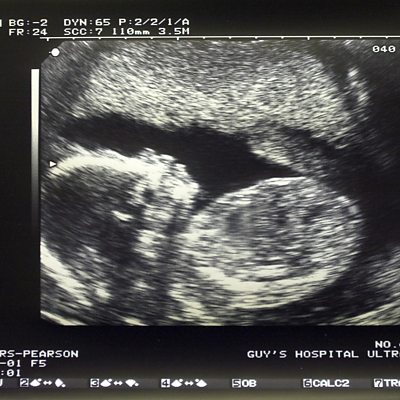

The Independent newspaper says that female foetuses are being illegally aborted in the UK's ethnic minority communities because families prefer to have sons. The paper had experts analyse the 2011 census and found differences in the sex ratio of children in some immigrant families. The ÃÛÑ¿´«Ã½ Asian Network phone-in discussed the issue - here some callers share their experience of Asian families having a preference for females. (the first clip in this montage includes a conversation in Punjabi - the male caller says 'I've had a girl, mother is fine' to his grandmother, and his grandmother replies 'don't worry about it'.)